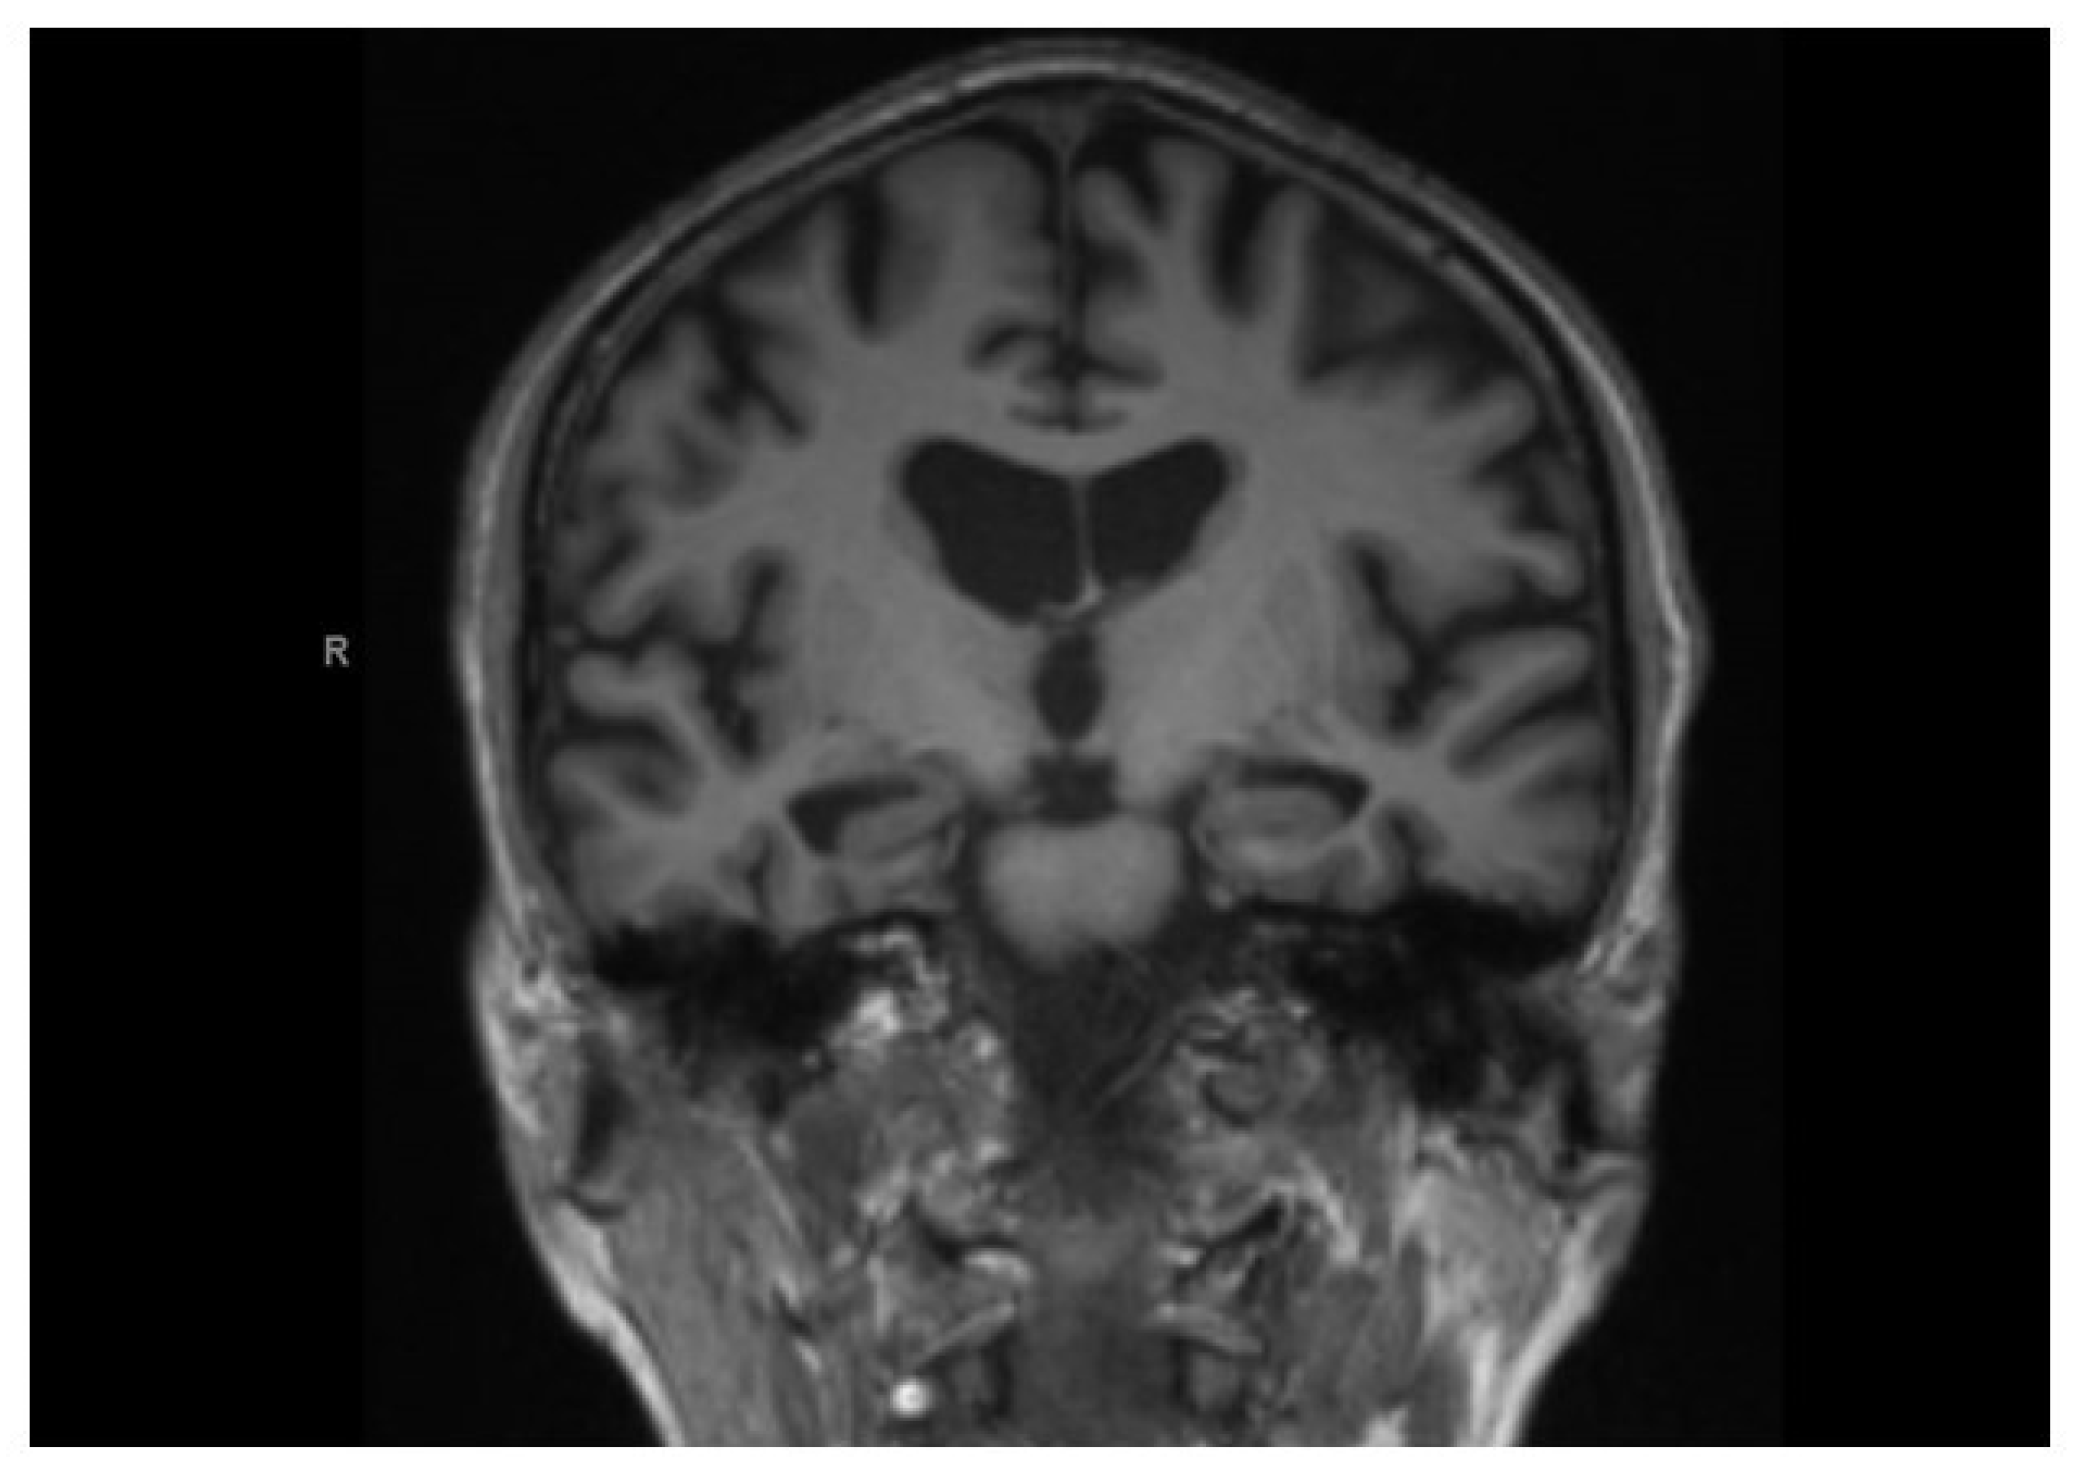

- Scheltens, P.; Leys, D.; Barkhof, F.; Huglo, D.; Weinstein, H.C.; Vermersch, P.; Kuiper, M.; Steinling, M.; Wolters, E.C.; Valk, J. Atrophy of medial temporal lobes on MRI in “probable” Alzheimer’s disease and normal ageing: Diagnostic value and neuropsychological correlates. J. Neurol. Neurosurg. Psychiatry 1992, 55, 967–972. [Google Scholar] [CrossRef]

| Subject | Age | Sex (0 = Female; 1 = Male) | Education (Years) | MCI Type | MoCA Score | Liquor Abeta 1–42 | Liquor Tau total | Liquor p-tau | Fazekas/MTA |

|---|---|---|---|---|---|---|---|---|---|

| 1 | 79 | 1 | 8 | Multiple-domain | 17 * | 1/2 * | |||

| 2 | 74 | 1 | 8 | Multiple-domain | 16 * | / | / | / | 0/2 * |

| 3 | 77 | 1 | 13 | Multiple-domain | 22 * | 555 * | 496 * | 94 * | 0/2 * |

| 4 | 76 | 1 | 8 | Multiple-domain | 15 * | / | / | / | 1/1 |

| 5 | 76 | 1 | 9 | Multiple-domain | 18 * | / | / | / | 3 */1.5 |

| 6 | 69 | 0 | 12 | Multiple-domain | 22 * | 511 * | 824 * | 191 * | 1/0 |

| 7 | 70 | 1 | 13 | Single-domain amnestic | 25 * | / | / | / | 1/1 |

| 8 | 80 | 0 | 13 | Single-domain amnestic | 21 * | / | / | / | 2 */1 |

| 9 | 71 | 0 | 23 | Multiple-domain | 17 * | 609 * | 590 * | 103 * | 0/1 |

| 10 | 78 | 0 | 13 | Multiple-domain | 20 * | 584 * | 517 * | 100 * | 1/1 |

| 11 | 77 | 1 | 13 | Multiple-domain | 20 * | / | / | / | / |